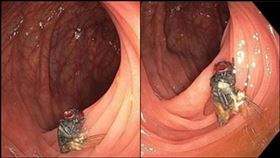

男照大腸鏡驚見完整蒼蠅躺腹 恐怖畫面曝

太驚悚!美國一名男子日前到大醫院做了例行性的大腸癌檢...